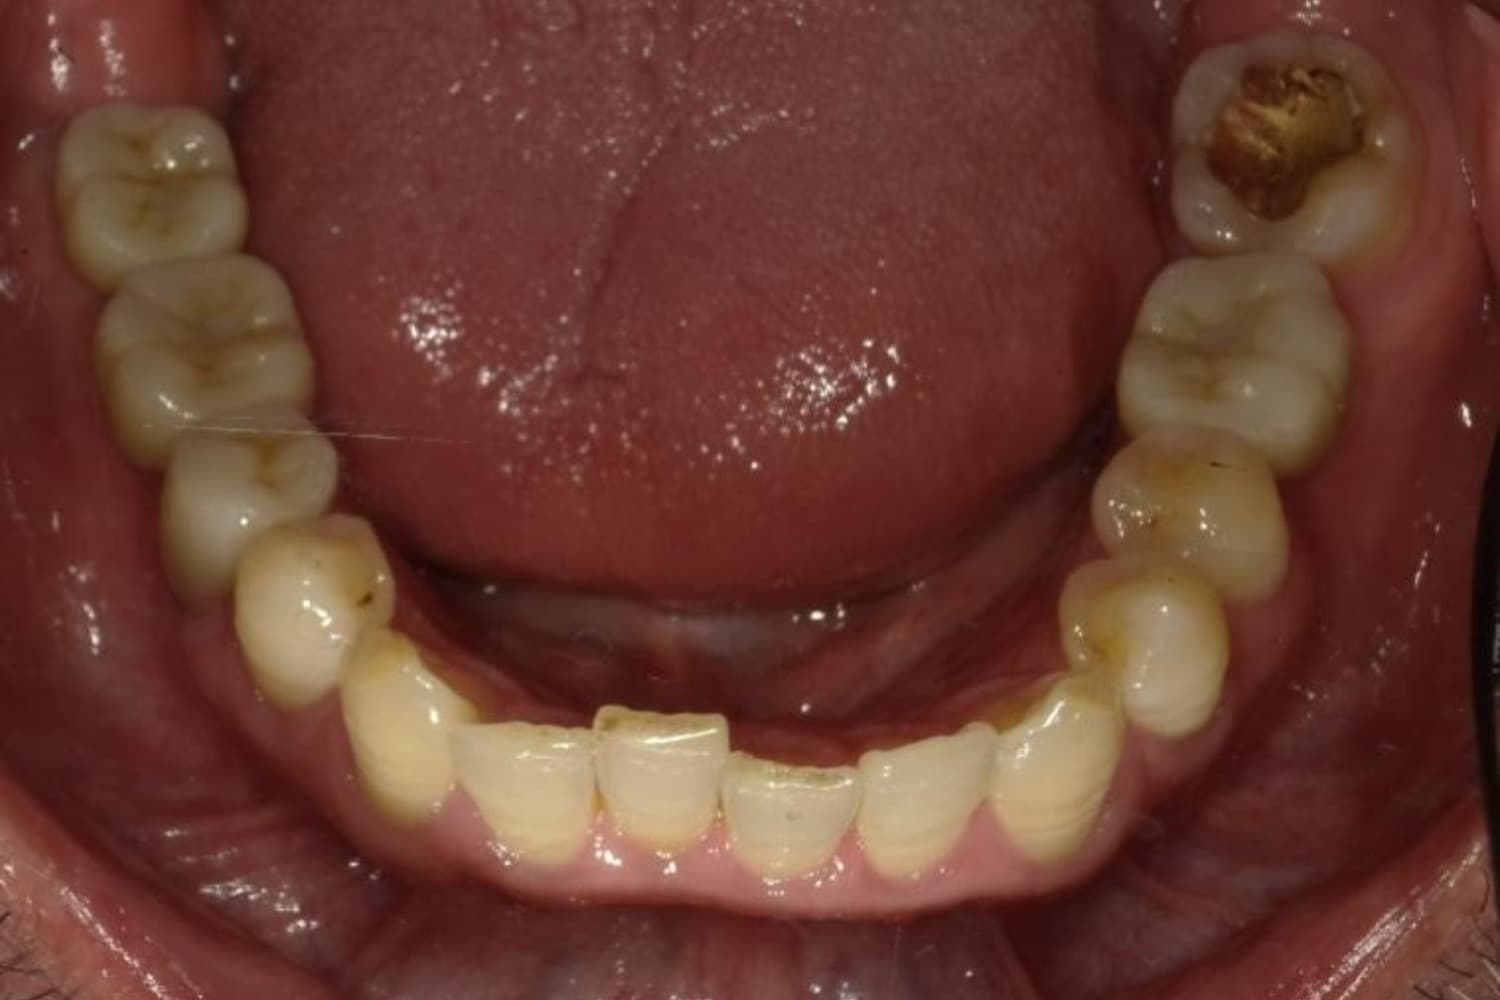

下顎大臼歯3本欠損症例

Before

After

左下第一大臼歯は保存が困難な状態であったため抜歯をおこないました。あわせて、ご来院時から欠損していた右下第一・第二大臼歯も含め、欠損部の補綴方法についてご説明し、インプラント治療を選択されました。

主訴

左下の第一大臼歯は別の医院で治療中でしたが、治療が思うように進まず、加えて他の箇所にも痛みが続いたことから、当院にご相談いただきました。

治療期間

10ヵ月

費用

140万円

副作用・リスク

インプラント治療は外科的な処置を伴い、多少の腫れや痛みが出ることがあります。 多くの場合は鎮痛薬で和らげることができます。